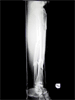

Progress

Good healing of fracture(s) and fixator removed three months later

Excellent limb alignment and good knee/ankle motion